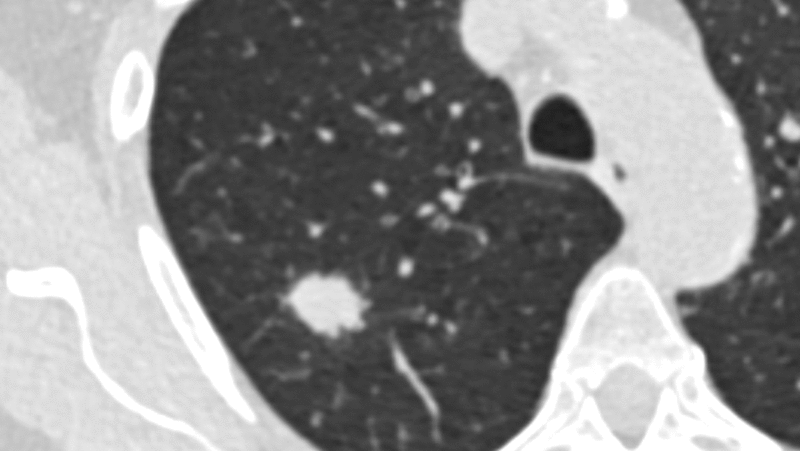

Jedes Jahr wird in Deutschland bei rund 57.000 Menschen Lungenkrebs diagnostiziert – mit oft tödlichem Ausgang, weil die Erkrankung typischerweise zu spät entdeckt wird. Voraussichtlich ab April 2026 soll ein neues Früherkennungsprogramm starten, das bei Menschen mit hohem Lungenkrebsrisiko mittels Computertomografie (CT) überprüft, ob verdächtige Veränderungen der Lunge vorliegen. Bisher ist geplant, dass das Lungenkrebs-Screening Personen zwischen 50 und 75 Jahren angeboten wird, die – vereinfacht gesagt – über 25 Jahre stark geraucht haben.

Verglichen wurden die Ergebnisse mit den Auswahlkriterien, die dem geplanten Lungenkrebs-Screening zugrunde liegen sollen und die ausschließlich das Alter und die Rauchhistorie berücksichtigen („NELSON-Score“). Alle Personen, denen anhand einer der beiden Scores ein hohes Lungenkrebsrisiko attestiert wurde, erhielten im Rahmen der Studie im Abstand von einem Jahr zweimal ein Niedrigdosis-CT. Verdachtsfälle wurden in interdisziplinären Fallkonferenzen überprüft und bei Bestätigung eine Behandlung eingeleitet.